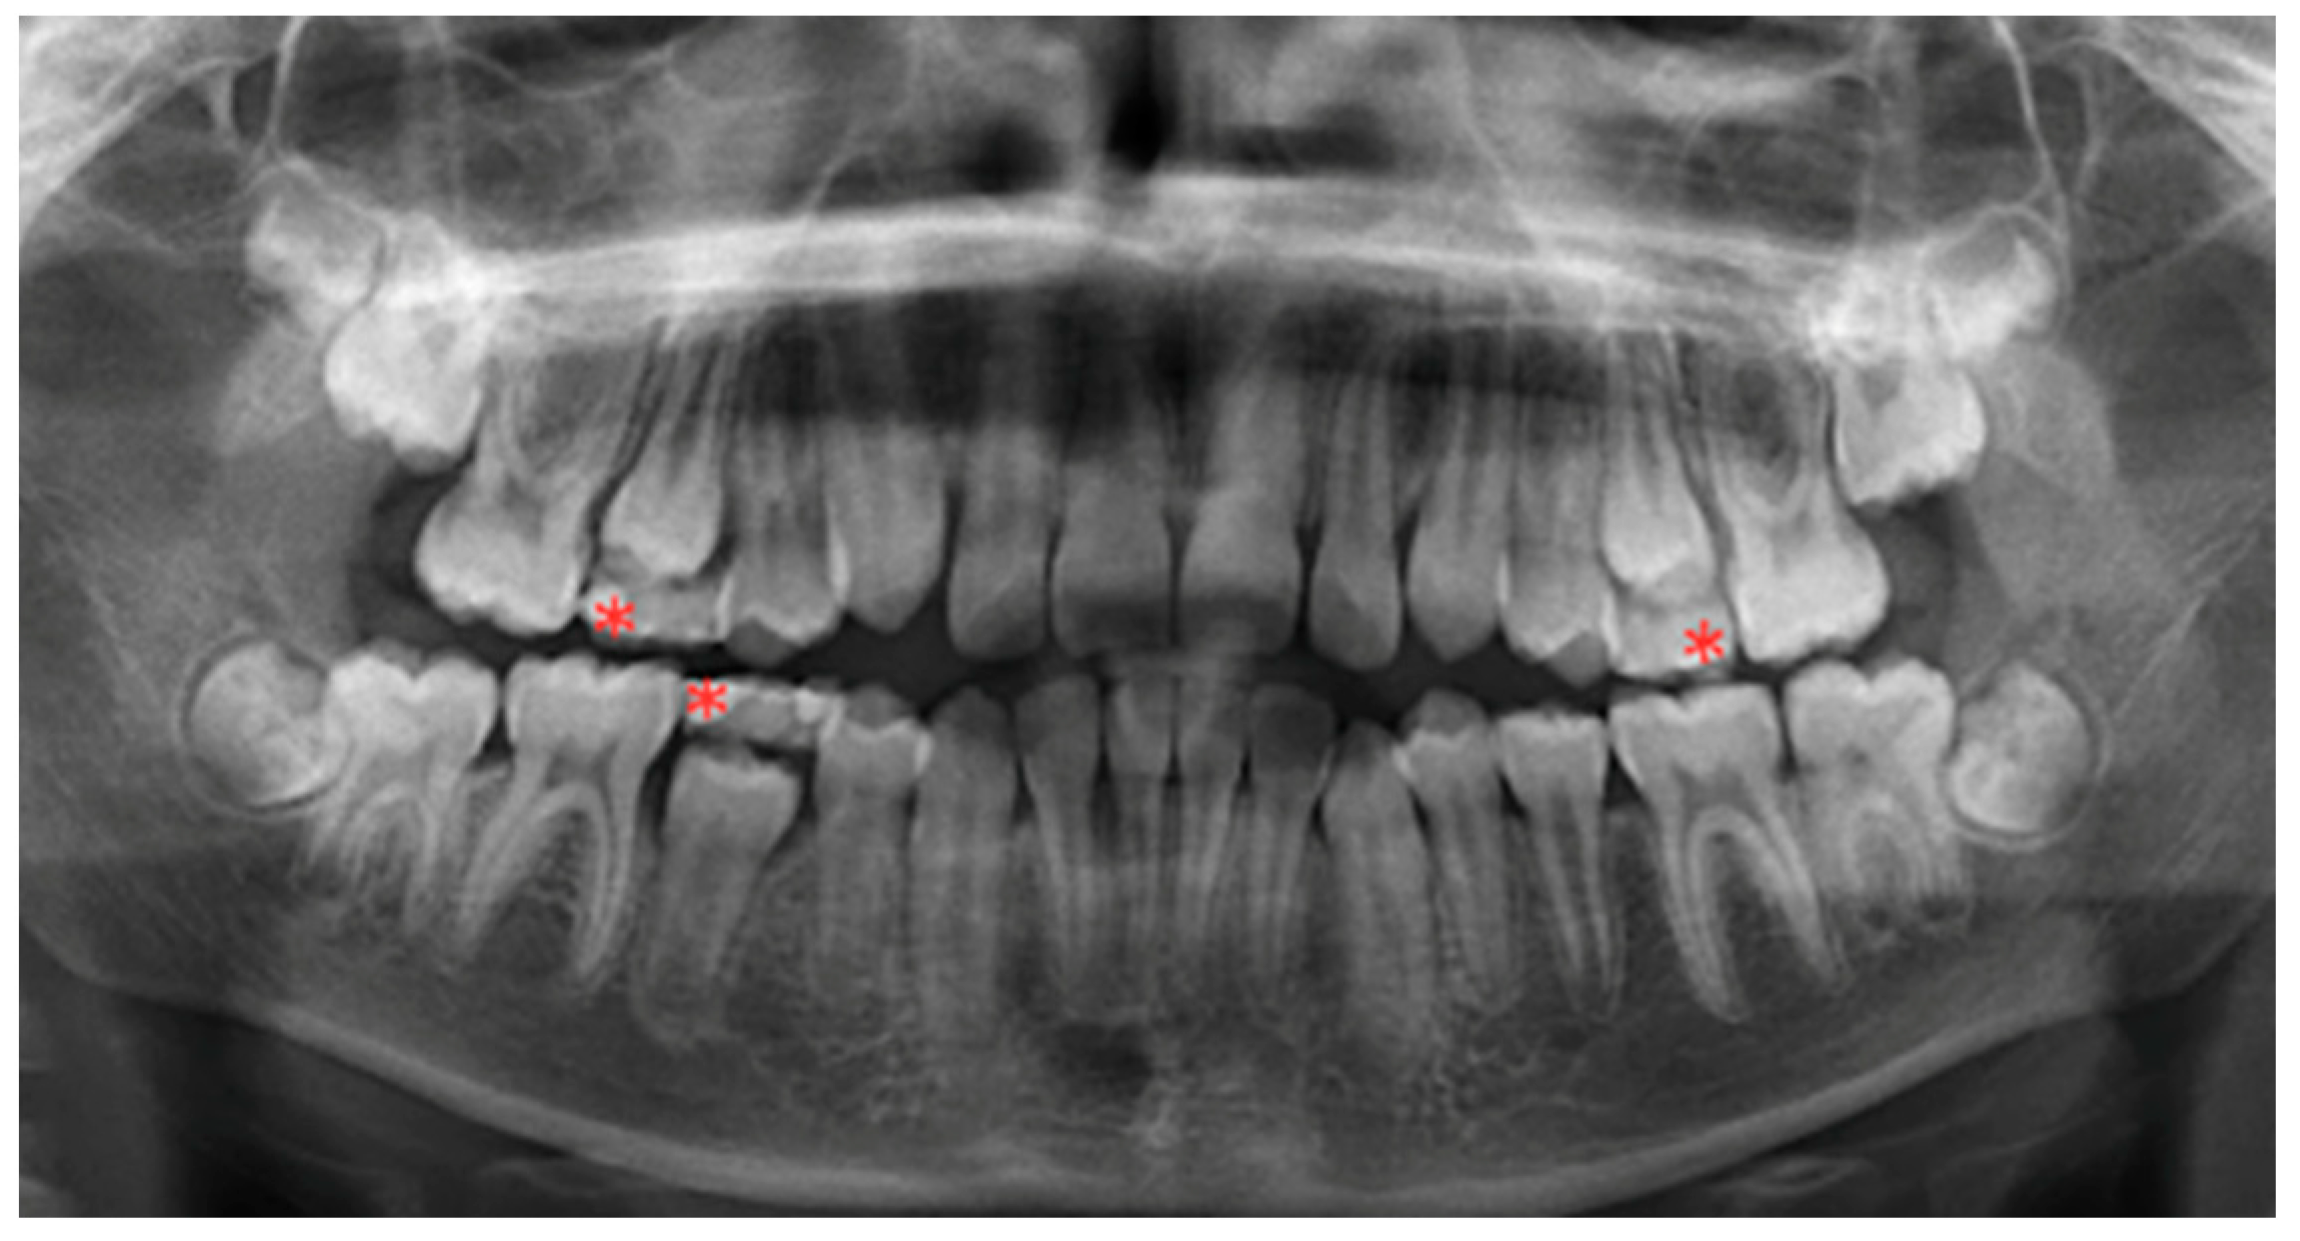

2.2. Panoramic Radiographs Evaluation and Characterization of PPT